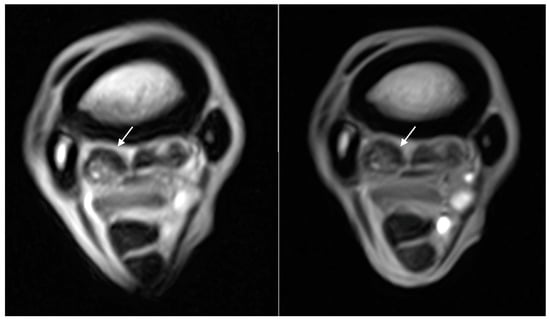

| Hyperintense signal on T1W GRE and T2*W GRE within the dorsal collagenous part of the PSL | 11/18 (61%) | 0/11 | 6/11 (55%) | 4/11 (36%) | 1/11 (9%) |

| Hyperintense signal on T1W GRE and T2*W GRE within the dorsal collagenous part of the PSL | Grade 0: 7 limbs Grade 1: 5 limbs Grade 2: 5 limbs Grade 3: 1 limb | Grade 0: 7 limbs Grade 1: 10 limbs Grade 2: 1 limbs Grade 3: 0 limbs |